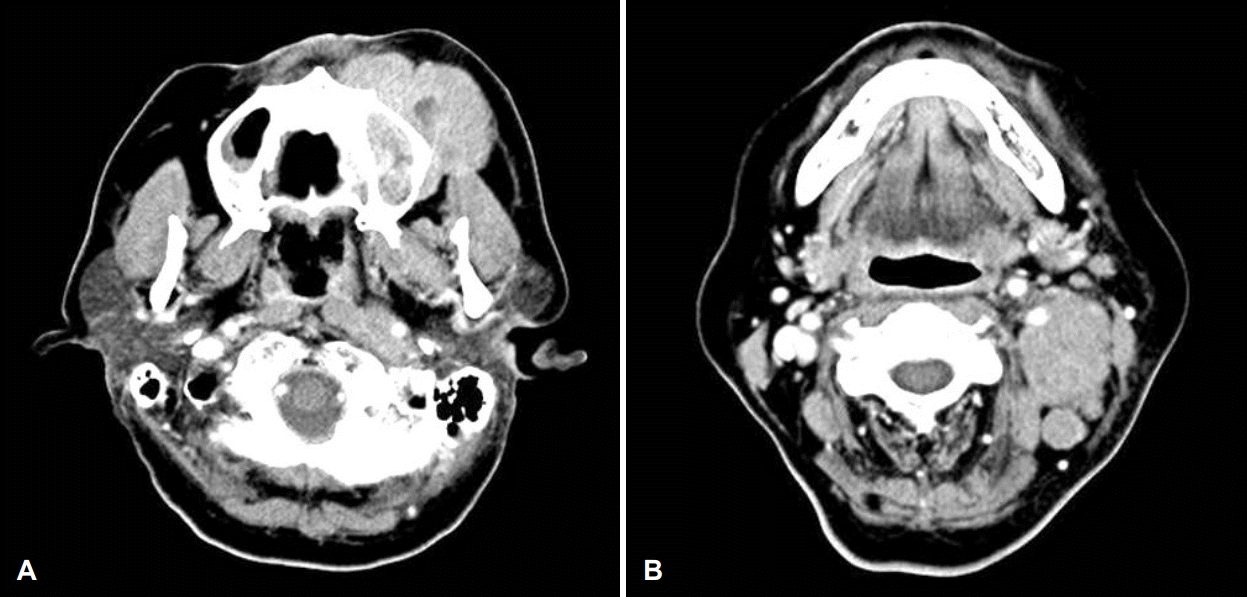

64세 여자 환자가 내원 5주 전 외부 치과에서 치아 신경치료를 받던 중 좌측 상 잇몸 및 안면 부종이 발생하여 콘빔 전산화단층촬영을 시행하고 절개 배농을 시도하였으나 실패하였다. 이에 영상상 발견된 부비동염 소견으로 타 외래에서 내원 2주 전 부비동 전산화단층촬영을 시행 후 양측 상악동 부비동염 의심 소견으로 내원하였다. 환자는 기저질환으로 고혈압, 당뇨 외 1992년 난소암으로 자궁전적출술 및 양측 난소 절제술 후 cyclophosphamide, adriamycin, cisplatin 3제 복합화학요법, 2003년에 유방암으로 절제 생검을 받은 과거력이 있었으며, 흡연력은 없었고, 가족력상 특이 소견은 없었다. 내원 당시 환자는 코 불편감을 호소하지 않았으며, 약간의 압통을 동반한 좌측 안면 부종 및 구강 시진상 좌측 제1, 2 소구치 주위 부종 소견(Fig. 1)을 보였으며, 비강 내시경상 좌측 비중격 만곡 외에 특이 소견은 없었다. 부비동 전산화단층촬영에서 양측 상악동에 골 점막 비후 및 연조직 음영을 동반한 석회화 소견이 관찰되었으나, 골 파괴 소견은 관찰되지 않았다(Fig. 2). 이에 환자에게 양측 상악동 진균성 부비동염 의심소견에 대한 수술적 치료의 필요성을 설명하였으나 환자는 치과 치료 후 발생한 좌측 안면 부종에 대한 우선적인 치료를 강력히 원하였고, 이에 치성 농양을 의심하에 본원 구강외과에 진료를 의뢰하였다. 이후 본원 구강외과에서 25번 치아 주위로 3번의 절개 및 배농으로 고름과 다량의 육아조직을 제거하고 항생제 치료를 하였으나 호전과 악화를 반복하였다. 6주 후 좌측 협측골의 누공이 상악동 내로 연결된 소견이 추가로 관찰되어 이비인후과로 다시 의뢰되었다. 재진료 시 여전히 코 불편감은 없었으나 좌측 안면 부종은 더욱 악화되었고, 비강 내시경상 좌측 중비도에 약간의 부종 소견을 보였다. 이에 양측 중비도 개창술을 계획하였다. 우선 우측 중비도 개창술 후 진균구로 의심되는 갈색의 석회화된 병변을 제거하였고, 이어서 좌측 중비도 개창술을 시행하였는데 진균구 의심 병변과 함께 매끈한 표면의 다소 견고한 연조직이 상악동 내부를 가득 채우고 있었다. 동결절편검사 결과, 해당 조직이 소세포암임이 진단되어 가능한 한도 내에서 미세절삭기를 이용해 일부 제거 후 수술을 종료하였다. 최종 조직검사 결과 hematoxylin & eosin 염색에서 세포질이 적고 핵이 과염색 되는 원형 및 방추형의 작은 세포가 관찰되었으며(Fig. 3A), 면역조직화학염색상 cytokeratin(Fig. 3B), CD56(Fig. 3C), synaptophysin(Fig. 3D)에 양성으로 폐외소세포암으로 진단되었다. 추가적으로 진균구에 대한 hematoxylin & eosin 염색상 균사는 아스페르길루스종으로 확인되었다(Fig. 3E).

Axial (A) and coronal (B) paranasal sinus CT scan. Periosteal mucosal thickening in the both maxillary sinus, and calcification in both maxillary sinus without bony destruction.